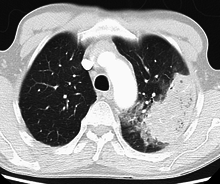

A chest radiograph is frequently used in diagnosis.[19] In people with mild disease, imaging is needed only in those with potential complications, those not having improved with treatment, or those in which the cause is uncertain.[19][48] If a person is sufficiently sick to require hospitalization, a chest radiograph is recommended.[48] Findings do not always match the severity of disease and do not reliably separate between bacterial infection and viral infection.[19]

X-ray presentations of pneumonia may be classified as lobar pneumonia, bronchopneumonia (also known as lobular pneumonia), and interstitial pneumonia.[51] Bacterial, community-acquired pneumonia classically show lung consolidation of one lung segmental lobe, which is known as lobar pneumonia.[29] However, findings may vary, and other patterns are common in other types of pneumonia.[29] Aspiration pneumonia may present with bilateral opacities primarily in the bases of the lungs and on the right side.[29] Radiographs of viral pneumonia may appear normal, appear hyper-inflated, have bilateral patchy areas, or present similar to bacterial pneumonia with lobar consolidation.[29] Radiologic findings may not be present in the early stages of the disease, especially in the presence of dehydration, or may be difficult to be interpreted in the obese or those with a history of lung disease.[20] A CT scan can give additional information in indeterminate cases.[29]